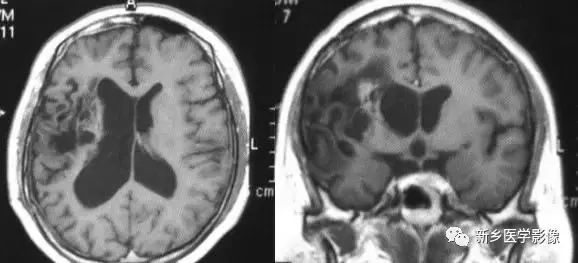

❷ 一侧大脑半球萎缩

可由许多原因引起,如脑梗死、外伤、出血及感染等。最常见的原因是血管闭塞引起大面积脑梗死。CT和MRI表现为:患侧侧脑室扩大、脑组织量减少,中线向患侧移位,严重者脑沟和脑回消失不见。